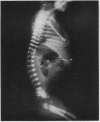

Images in this article